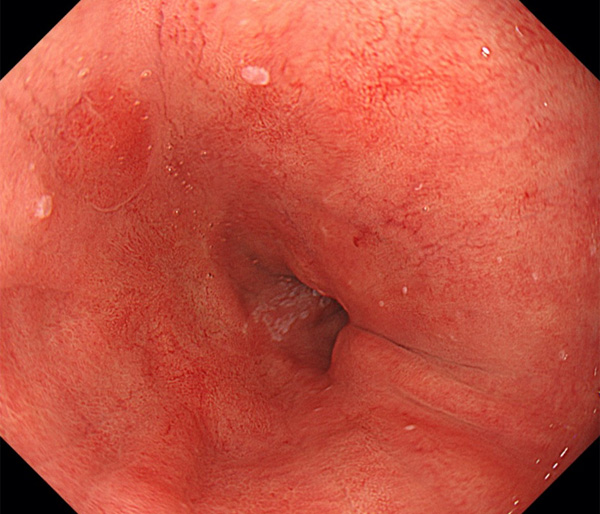

内視鏡所見と病理組織像の1対1対応が可能な症例を公募いたします。主にLSBEに発生した早期癌(HGDを含む)を対象としますが、興味深い症例であればSSBE癌でも結構です。採否は世話人へご一任ください。

症例呈示希望者は応募用紙に記入の上、代表的な内視鏡(2枚)、切除標本(新鮮、固定)、切り出し図、マッピング、代表的組織像とともに、Barrett 食道研究会事務局 barrett.shinshu@gmail.comへお申し込み下さい(10MB以下でお願い致します)。

特に、本邦では極めて稀なlong segment Barrett’s esophagus(LSBE)から発生した早期癌は、診断に難渋する場合も多く、欧米ではランダム生検による検出が標準的とされています。背景のBarrett食道もろとも全体を内視鏡切除+ラジオ波焼灼する欧米と異なり、ESDで内視鏡的な局所切除が基本の本邦では、存在診断+範囲診断(特に水平)を的確に行うことが不可欠です。

そのためには、一流の病理医による組織学的診断とエキスパート内視鏡医による拡大内視鏡像との一対一対応を徹底的に行うことで、『本来、見えないであろう拡大所見の先にある組織構築像が診えてくる』所まで内視鏡診断レベルを上げていく必要があります。その実現には、一対一対応を追究した症例(特にLSBE発生例)1例でも多く経験するしかありません。本研究会でBarrett食道腺癌(LSBE発生早期病変)を共に学び、拡大内視鏡像の一歩先を診るスキルを習得しましょう!一人でも多くの皆様のご参加をお待ちしています。